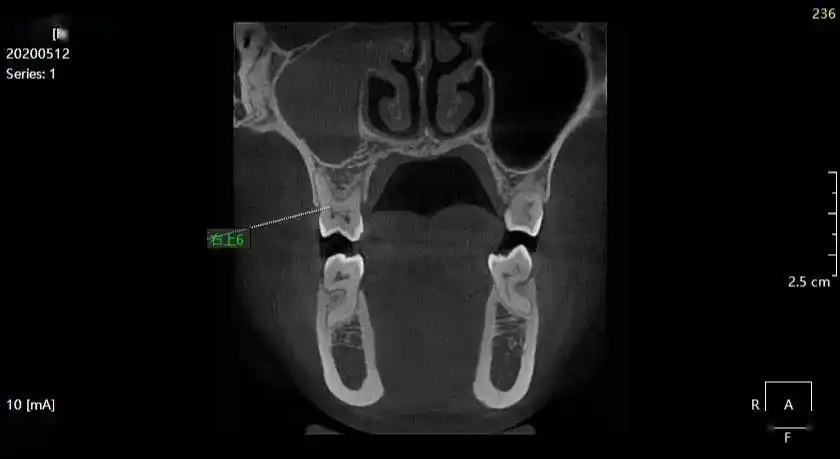

右下:上颌骨额突骨折左下:上颌窦前壁骨折左上:颚骨骨折下颌骨双侧

李xx20200512上颌窦炎ct158xxxx0907